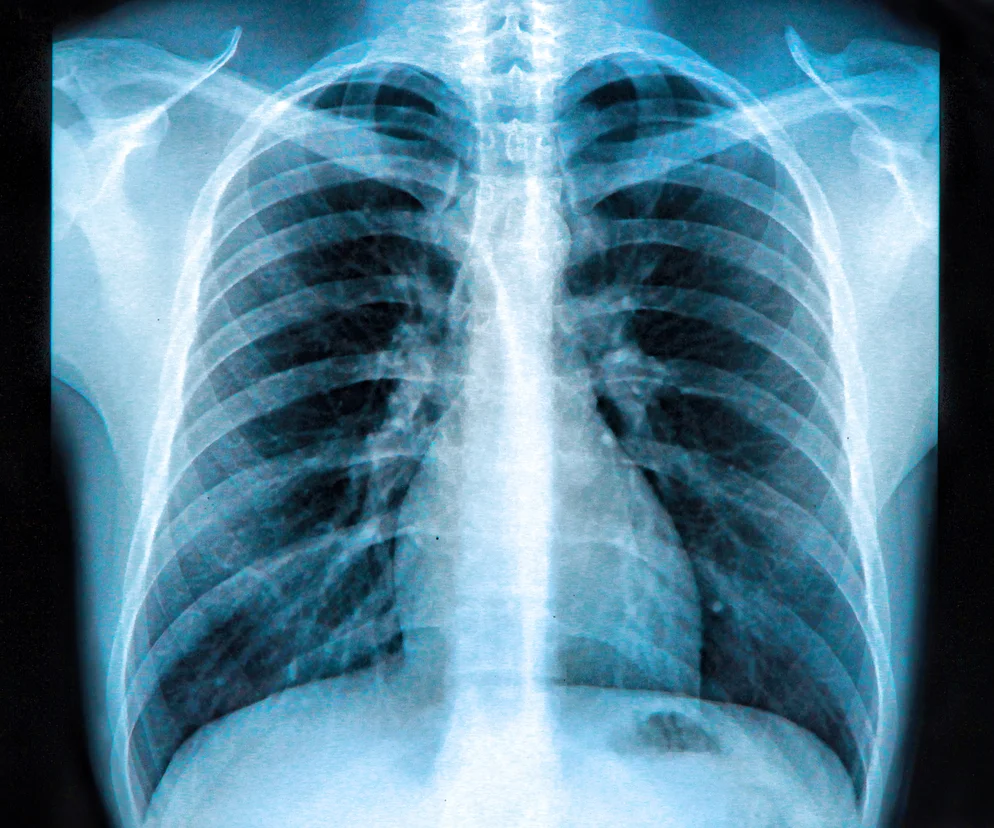

Rozpoznanie lejkowatej klatki można postawić już gołym okiem, lecz w celu określenia jej stopnia zaawansowania oraz wdrożenia niezbędnych działań terapeutycznych konieczne jest wykonanie dokładniejszych badań. Podstawę stanowią badanie radiologiczne – zdjęcie RTG klatki piersiowej i badanie za pomocą tomografii komputerowej (KT). To właśnie w badaniu KT możemy wyznaczyć tzw. wskaźnik Hallera – stosunek szerokości klatki piersiowej do jej głębokości(najkrótsza odległość między mostkiem a kręgosłupem). Pozwala on na obiektywną ocenę stopnia ciężkości wady – wskaźnik wynoszący powyżej 3,25 pozwala stwierdzić postać ciężką, która wymaga zabiegu operacyjnego(norma wynosi 2,5). Ważna jest również ocena funkcjonowania układ oddechowego i krążenia – niezbędne jest wykonanie spirometrii, badania EKG i ECHO serca. W przypadku podejrzenia wrodzonego zespołu, któremu współtowarzyszy szewska klatka, konieczne może być wykonanie badań genetycznych.